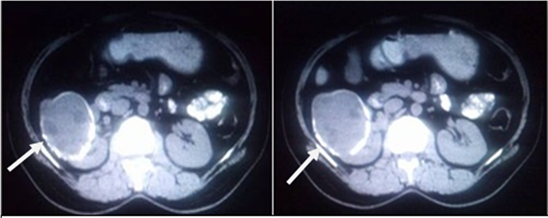

Figure 7. Class CE2 Hydatid cyst in right kidney in a 69 yr old gentleman with history of right loin pain. Plain and CECT abdomen showed well defined, rounded, iso dense lesion, with thick wall calcifications, and few daughter cysts within with differential attenuation, with no enhancement on postcontrast.

attenuation wall at unenhanced CT due to laminated membrane is hyperdense on non-contrast CT; may show indirect signs of infection and/or communication with the biliary tree such as gas/ air fluid levels or fat inside the cysts [Figure 14] [2] [3] [5] .

Type IIC lesions appear as relatively high attenuation round or oval masses with scattered calcifications and occasional daughter cysts. These findings represent degeneration of old cysts with amorphous and tenacious content [Figure 7 and Figure 8].

Figure 16. Class CE2 Hydatid cyst in left kidney in a 32 yr male patient with left flank pain. Plain and CECT abdomen showed oval shaped, multivesicular cystic lesion with thin high attenuation rim on plain CT with no obvious enhancement on postcontrast with “Honey comb-like” appearance in left kidney.